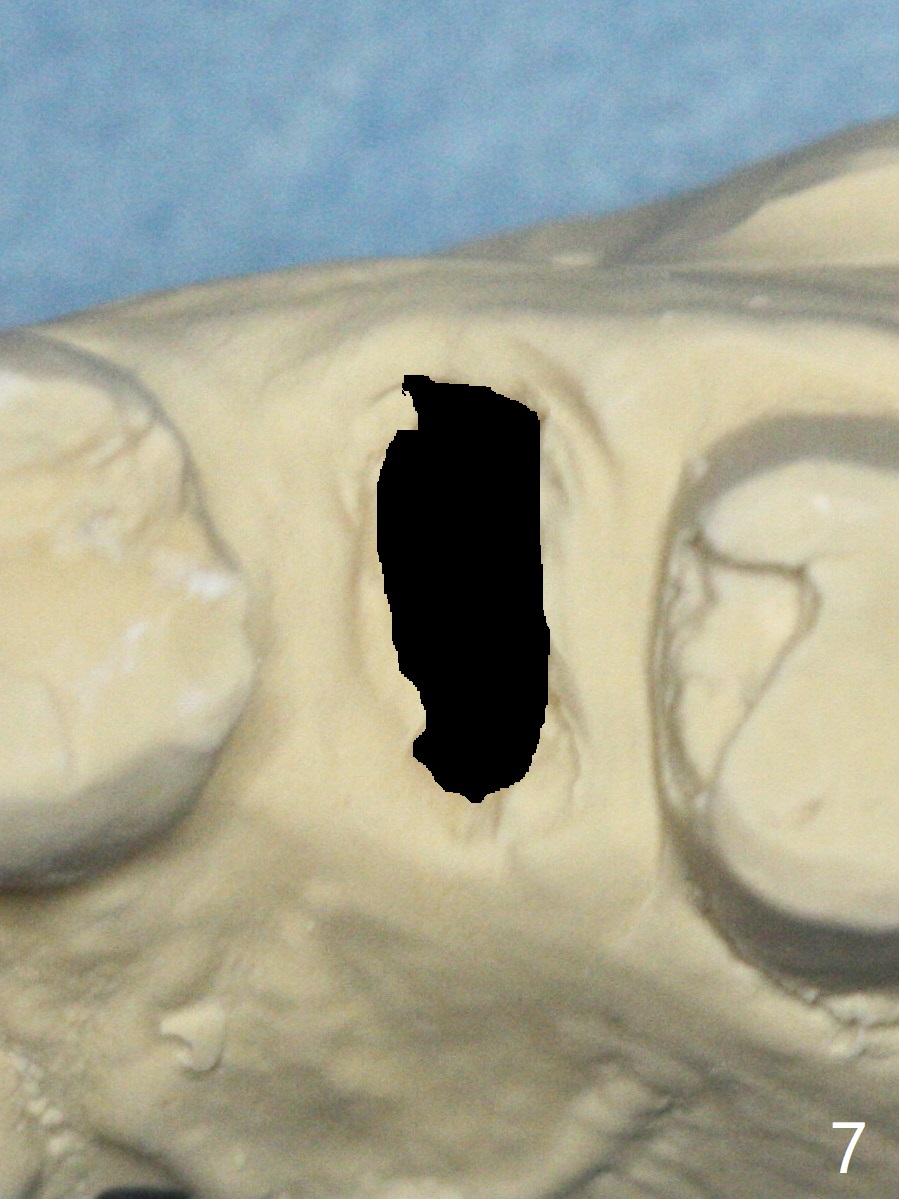

A 49-year-old woman has loose splinted crowns between #13 and 14. After removal of the crowns, the tooth #13 is found non-salvageable (Fig.1). A 4 or 4.5 x 8.5 or 10 mm implant should be able to achieve primary stability because of engagement of the implant into the mesial and distal walls of the socket and the sinus floor. Splinted provisional should provide with additional retention. There is no much need for socket shield, since there is no mesial or distal crestal bone loss (associated with food impaction). If the crown is short, there is no concern about buccal gingival recession. In fact the mesial papilla is more apical than the distal one (Fig.2 *), corresponding to the more apical crest (Fig.3 *). To prevent further mesial crestal loss post extraction, socket shield seems necessary. There appears that the implant is placed distal enough so that a small portion of the mesial root (Fig.4,5 R) is able to be saved. Fig.6 is the occlusal view of the residual root of the tooth #13. The mesial sheath will be kept (Fig.7,8, as compared to Fig.3).